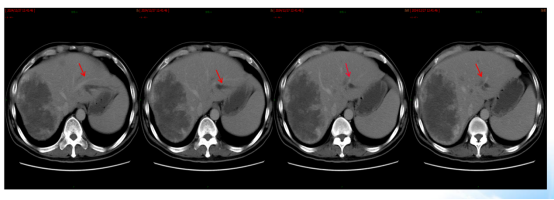

治疗4周期后,肝脏转移灶较基线缩小约20%(图5/6),CEA从532.4 ng/ml降至217.3 ng/ml,CA199从344.2 U/ml降至172.9 U/ml,评估为SD。

图5. 2024年10月24日CT:肝脏多发转移瘤,较大者位于右半肝,致肝右静脉、门静脉右支受侵

图6. 2024年10月29日MRI:肝脏多发转移瘤,伴有肝右静脉及门静脉右支受侵

肝脏病灶稍缩小(图8/9),评价为SD。但出现支架旁包裹性积气、积液,提示局部穿孔伴脓肿(图10)。

图8. 2024年12月27日CT:肝脏多发转移瘤,伴有肝右静脉及门静脉右支受侵,较2024年10月24日稍缩小

图9. 2024年12月29日MRI:肝脏多发转移瘤,伴有肝右静脉及门静脉右支受侵,较2024年10月24日稍缩小